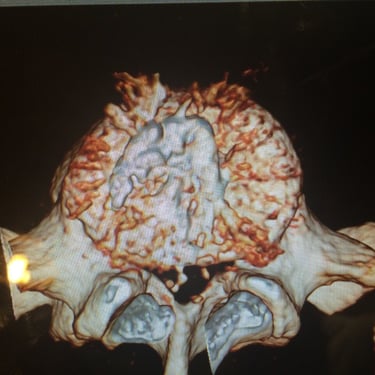

An intriguing case involved severe herniation and disc rupture between L4 and L5 vertebrae, causing intense pain. Opting out of surgery, the patient chose to try Discogel. Due to severe foraminal stenosis from the extruded disc, the Discogel injection was cautiously prolonged to one hour. Post-injection CT scan revealed effective penetration into fragmented disc components in the narrowed foraminal space.

The patient's pain gradually diminished after 4-5 weeks, and complete relief was achieved after several months.

The first image is six months post-injection, and the second image is three years post-injection."

Important Note: Foraminal disc herniation and migration into the intervertebral foramen significantly reduce the likelihood of a favorable response to Discogel injection and are not recommended for such cases.